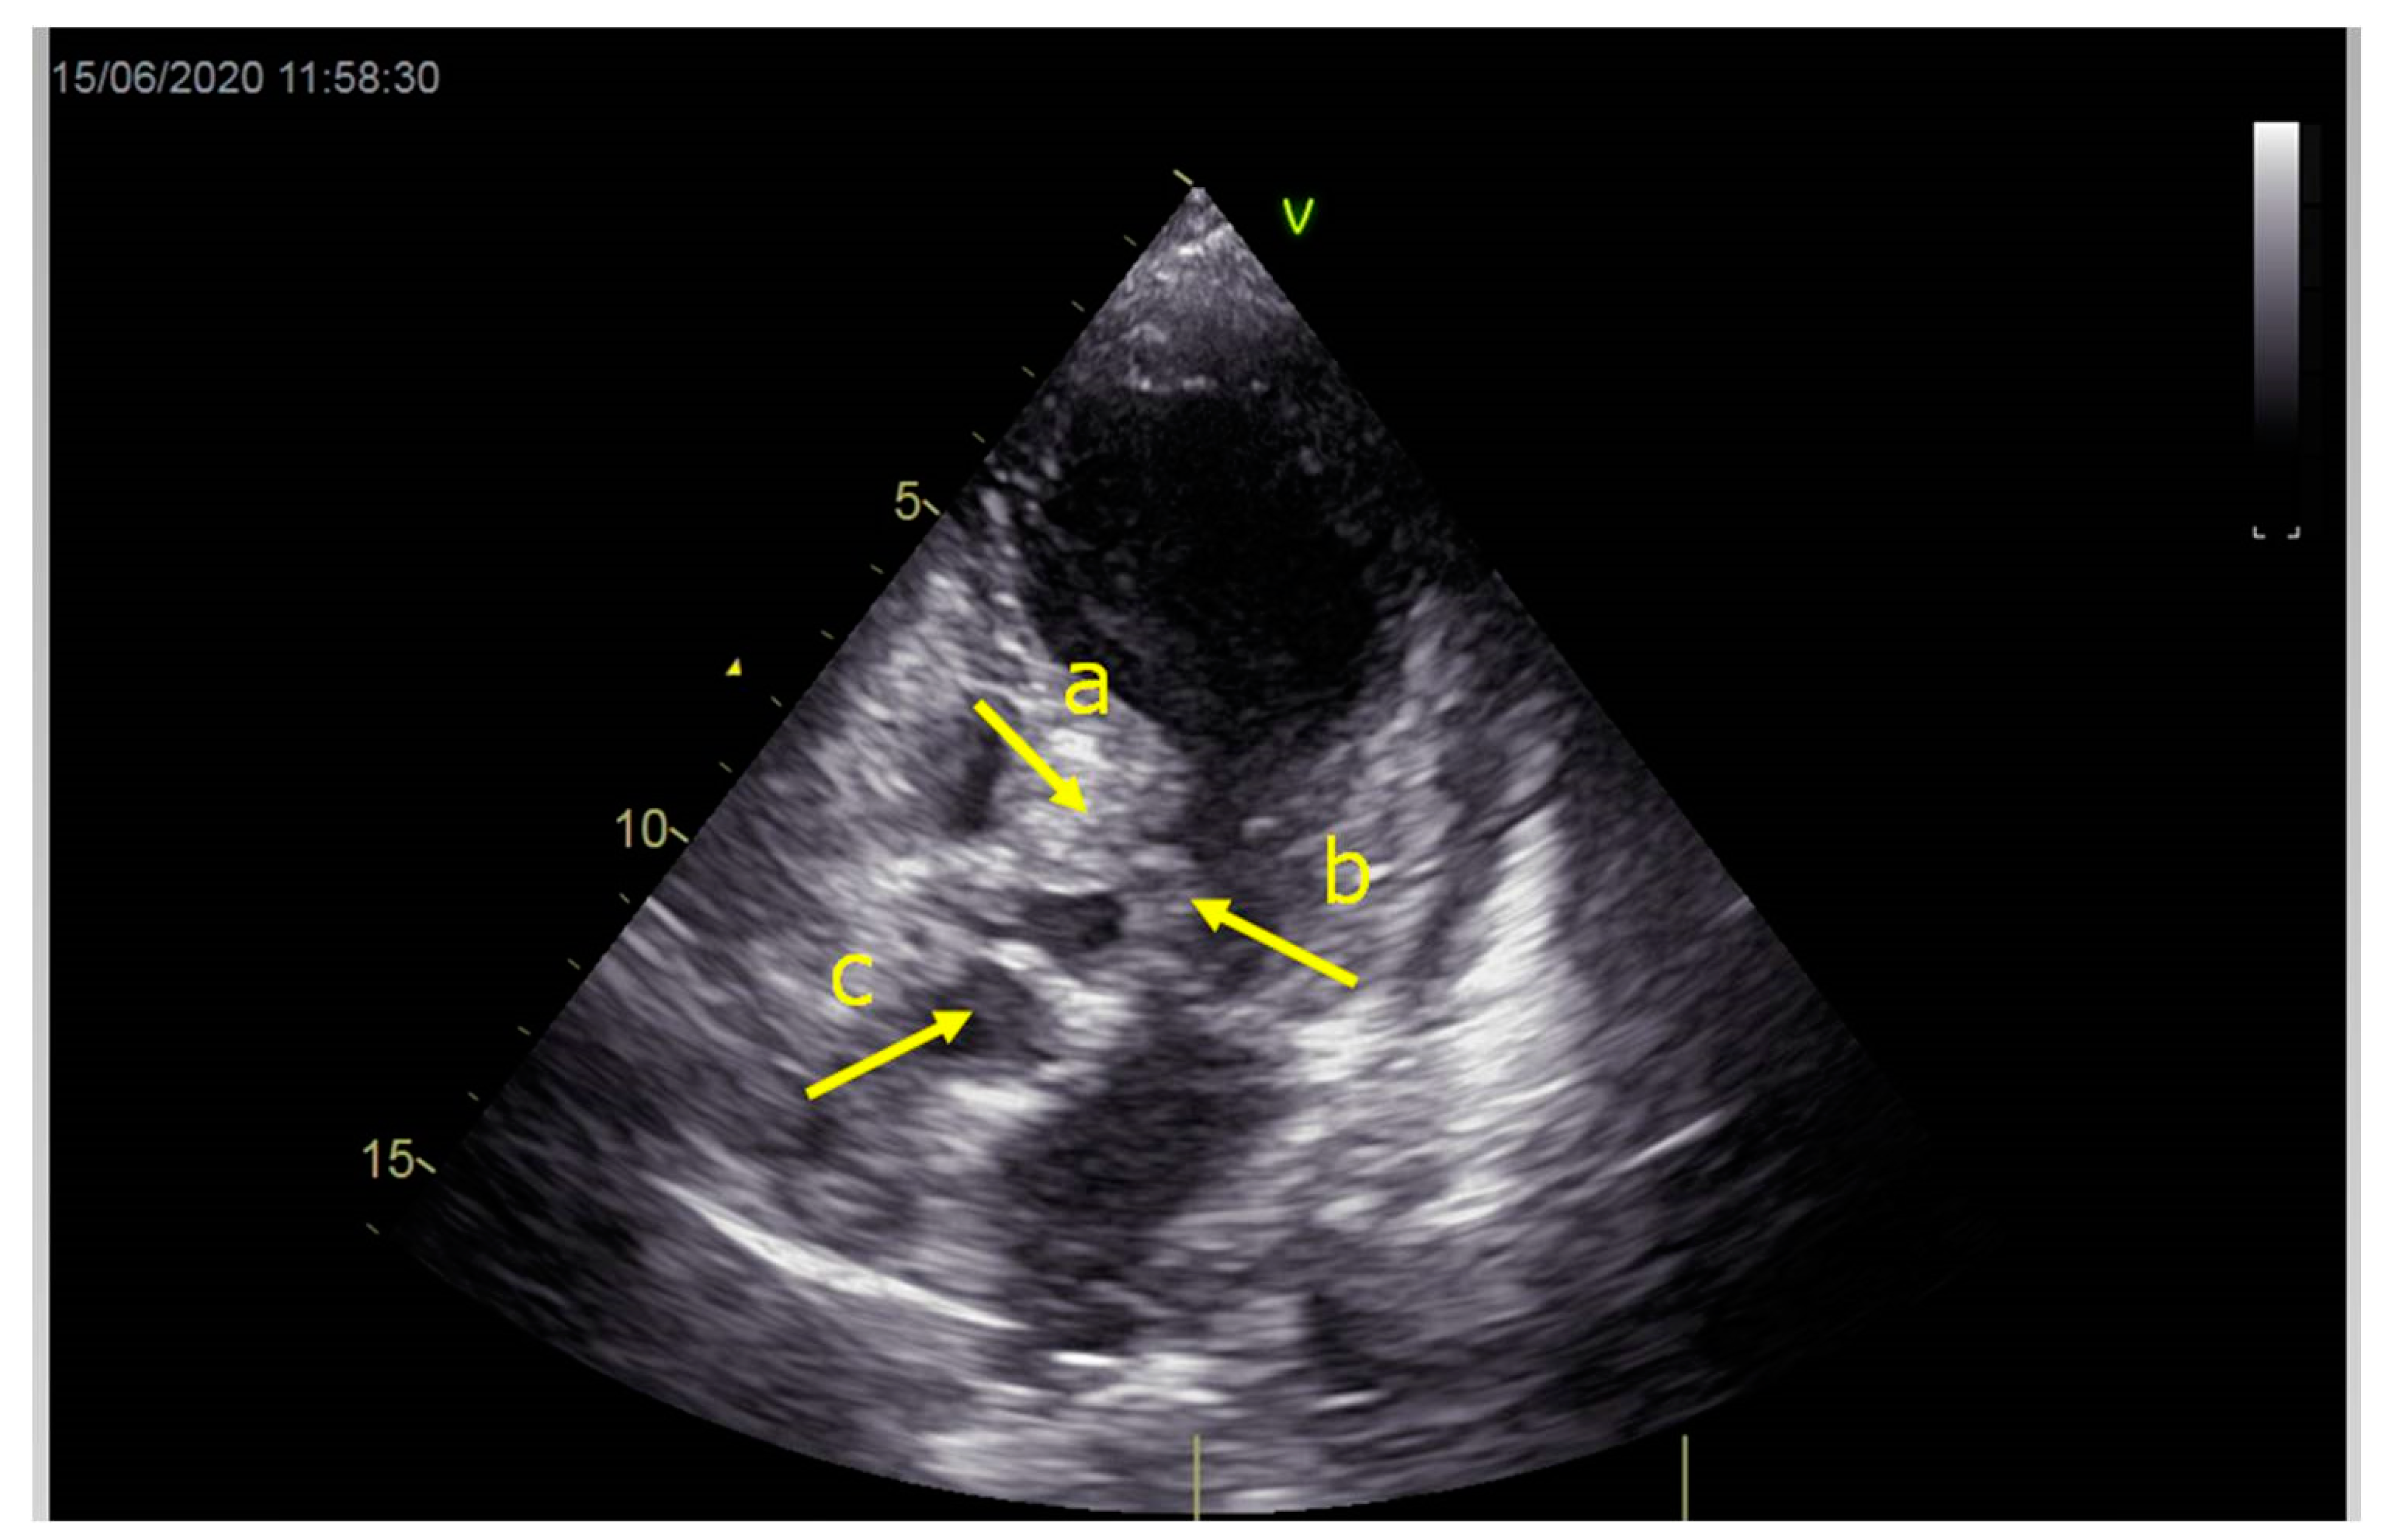

As a result, the patient was referred to a specialized medical institution. Upon admission, the patient was conscious, confused, hypotensive (TA 80/50 mmHg), with a heart rate of about 110/min, and showing clinical signs of hypoperfusion and cardiogenic shock, Killip IV. The medical staff administered sedation, inserted an endotracheal tube, and placed her on invasive mechanical ventilation. The patient was given crystalline solutions, inotrope, and vasopressor medication. An urgent echocardiographic examination was performed due to a rough systolic murmur over the precordium. It revealed akinesia of all medioapical segments of the left ventricle and akinesia basally inferior, where the myocardium was fibrously altered. Other hyperkinetic basal segments formed a dynamic obstruction of the left ventricular outflow tract (LVOTO) with turbulent flow and moderate mitral regurgitation (Figure 2 and Figure 3). The maximum gradient above the LVOT was 160 mmHg (Figure 4). The aortic valve area was 1.8 cm2 (Figure 5). The ejection fraction of the left ventricle (LVEF) was estimated to be 25%. The examination also revealed pericardial effusion with separation between pericardial layers along the right ventricle and atrium of up to 1.2 cm, but without any signs of tamponade.

Figure 2.

Echocardiography registered basal hyperkinetic segments of the left ventricle and formed a dynamic obstruction of the left ventricular outflow tract (a—LVOT, b—cuspi anterioris valvulae mitralis, c—aortic valve).